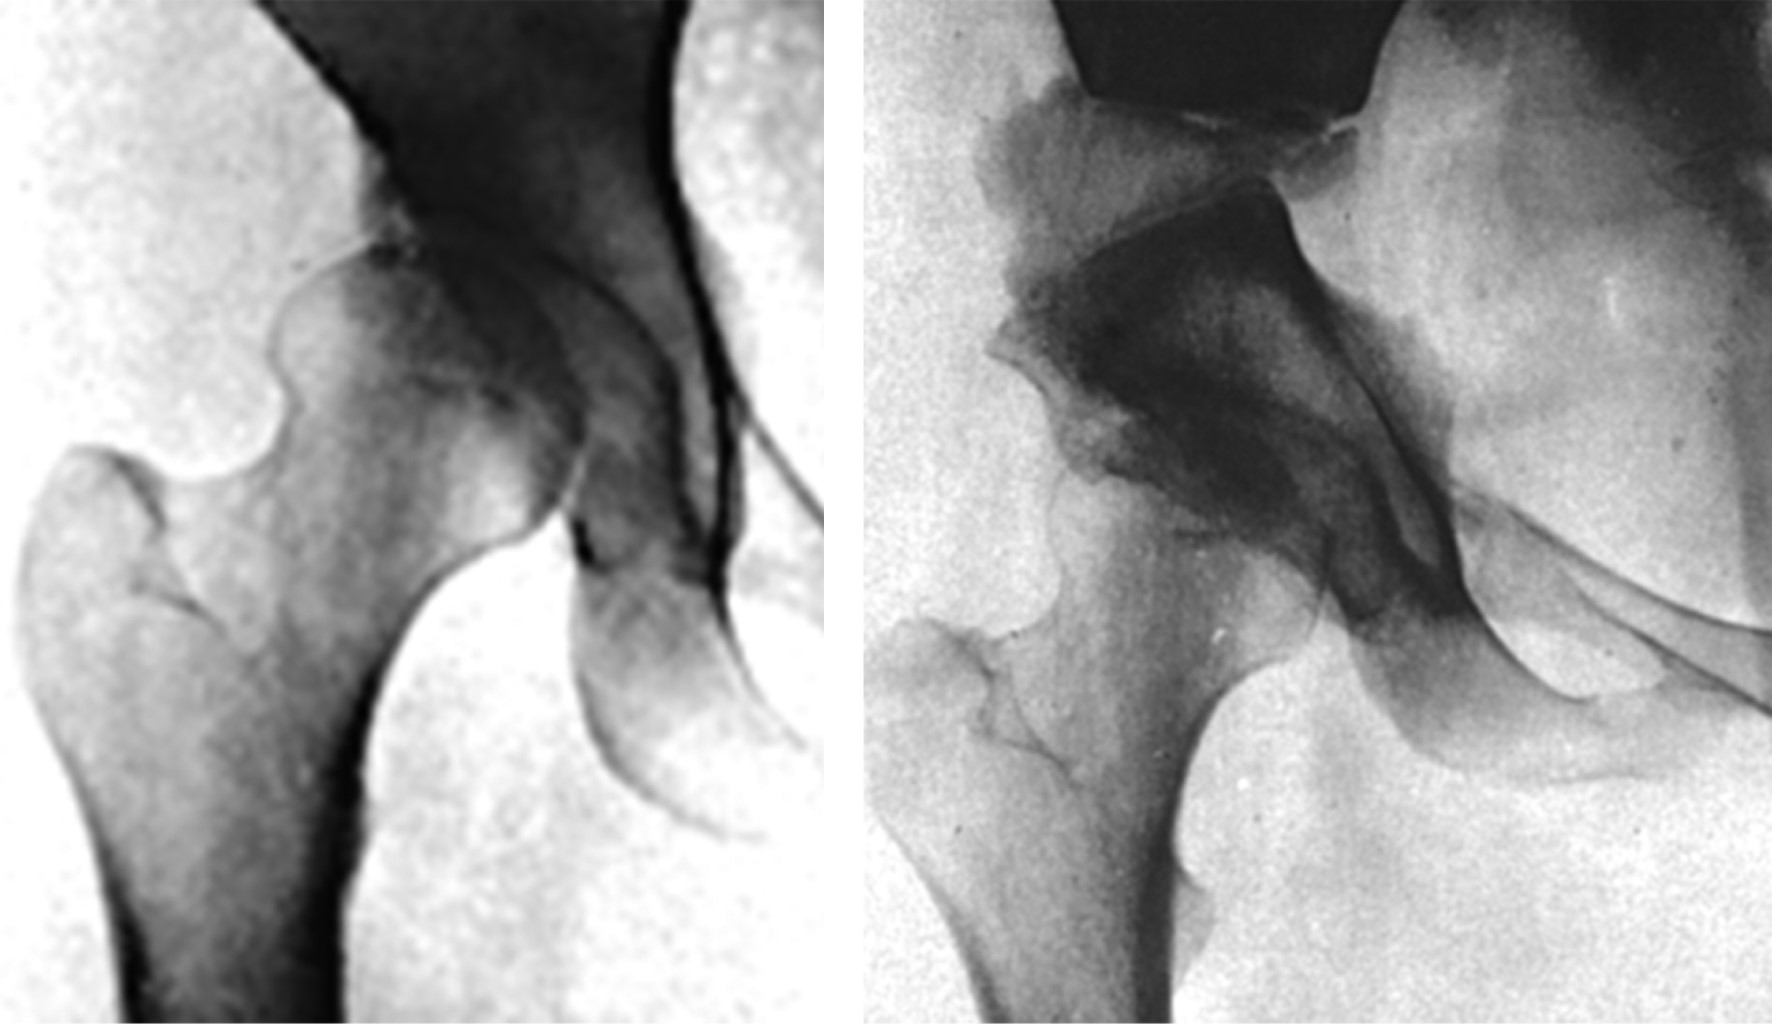

De manera simultánea a la introducción de las hemiprótesis con vástagos que invaden francamente el endostio metadiafisiario, se desarrollan las primeras prótesis "ultracortas" que tienen un vástago que sólo invade el cuello y parte de la metáfisis proximal. Los argumentos para utilizar estos diseños fue que por experiencia clínica acumulada con las copas de recubrimiento tipo Smith-Petersen, se sabía que con estas copas no se obtenía una estabilidad satisfactoria, por lo que se diseñaron estos implantes ultracortos con la esperanza de que con un vástago intraóseo cérvico-metafisario se pudiera obtener una mejor estabilidad. Así, en 1950 los hermanos Robert y Jean Judet35 proponen el diseño de prótesis con "vástagos ultracortos". Estas prótesis fueron fabricadas en un inicio con vidrio y posteriormente con el plástico acrílico (Plexiglas®) (Figura 13A y B). Poco tiempo después otros autores, incluyendo a Thompson, diseñan modelos similares fabricados con Vitalium® (Figuras 13C y 14).

Ya se ha mencionado que las prótesis de recubrimiento usadas hasta entonces no proporcionaban una estabilidad adecuada. Charles O. Townley agrega un largo y delgado vástago intramedular a las copas de recubrimiento (Figura 15A) para intentar ofrecer mayor estabilidad. Este modelo fue sustituido por el mismo autor con otros prototipos (Figura 15B y C). Aunque esta idea mejoró la estabilidad, no fue capaz de resolver el problema de aflojamiento aséptico a mediano y largo plazo.

Ya que los modelos iniciales de las prótesis con vástagos ultracortos o cortos tuvieron muy poca aceptación, la comunidad médica buscó alternativas más seguras en cuanto a estabilidad y longevidad a largo plazo. En esta búsqueda, en 1966 George Kenneth "Ken" McKee y John Watson Farrar46 presentaron un diseño de prótesis total fabricado en Vitalium® que ofrecía una alternativa diferente a las hemiprótesis hasta esa época empleadas (Figura 16). Esta idea marcó el inicio de las prótesis totales no cementadas metal-metal.

En su propuesta de diseño, McKee y Farrar incorporaban un acetábulo metálico a un vástago femoral con cuello delgado (modelo Thompson). El modelo del vástago Thompson tiene un cuello delgado que disminuye la posibilidad de colisión entre el cuello femoral óseo con el borde del acetábulo. Hay que recordar que el cuello óseo nativo debía conservarse en los vástagos cortos empleados en esa época.

En pleno auge del concepto de prótesis totales y tribología metal-metal, "Ken" McKee y Watson-Farrar hacen una serie de intentos para desarrollar una prótesis total metal-metal donde el principal problema era la estabilidad acetabular. En su último y tercer intento diseñaron un acetábulo provisto de un tornillo que roscaban en el acetábulo (Figura 17A), con lo cual se buscó resolver la inestabilidad del acetábulo diseñado por ellos años a atrás.47 Como contraparte continuaron empleando un vástago tipo Thompson no cementado. En 1970 adoptan el cemento óseo como medio de fijación, mejorando considerablemente los resultados de esta prótesis. En esa misma época (1968), Peter A. Ring47desarrolla un acetábulo muy parecido a el propuesto por McKee y Farrar (acetábulo roscado en ilíaco), pero utiliza como contraparte femoral un vástago tipo Moore, obteniendo mucho mejores resultados que los alcanzados por McKee con el vástago modelo Thompson (Figura 17B).